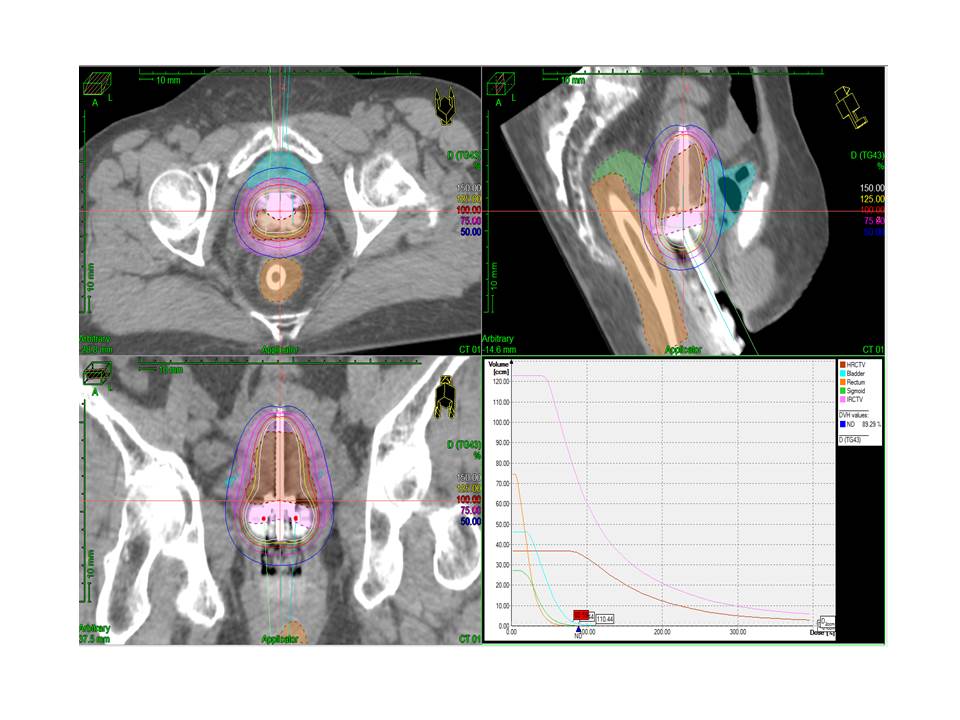

The plain radiographs may either be unremarkable or may demonstrate a radiolucent soft tissue mass of fat opacity. Layanan Unggulan Unit Pelayanan Onkologi Radiasi

Scan computed tomography (ct) atau magnetic resonance imaging (mri) pada . Pemindaian perfusi miokard (misalnya melalui mri jantung atau skintigrafi. Pemeriksaan mri menunjukkan hasil yang. Gejala paling umum kanker serviks adalah perdarahan yang tidak normal. (pada beberapa kasus, skrining tidaklah berkaitan dengan faktor risiko dan anda tetap harus menjalani uji skrining seperti pap smear untuk kanker serviks.). Uterine cervical neoplasms, pet/ct and cervical cancer | researchgate,. Menggunakan electronic portal imaging device (epid). Apabila hasil pap smear menunjukkan adanya sel abnormal pada leher rahim, .